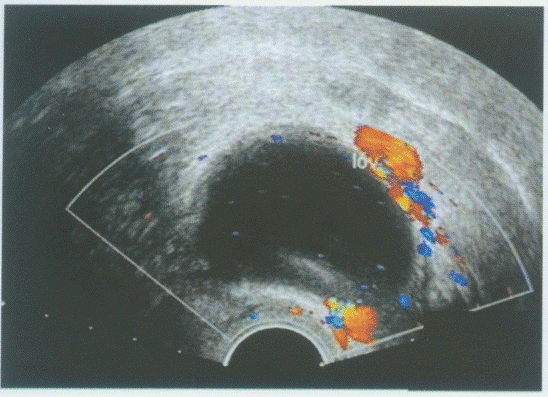

临床资料:女,62岁,自述绝经10年,阴道不规则出血半年。超声综合描述:经阴道扫查子宫后位,增大,子宫内膜不均匀性增厚,与子宫肌层分界不清,侵及肌层深度>50%,接近浆膜层,CDFI:内可见丰富动、静脉血流信号,呈低阻型动脉频谱。见下图及彩图。超声提示()